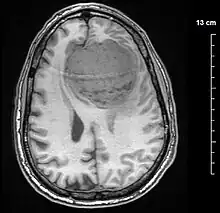

A meningioma that previously had been operated on, with surrounding edema

Meningiomas are visualized readily with contrast CT, MRI with gadolinium,[22] and arteriography, all attributed to the fact that meningiomas are extra-axial and vascularized. CSF protein levels are usually found to be elevated when lumbar puncture is used to obtain spinal fluid. On T1-weighted contrast-enhanced MRI, they may show a typical dural tail sign absent in some rare forms of meningiomas.[17]